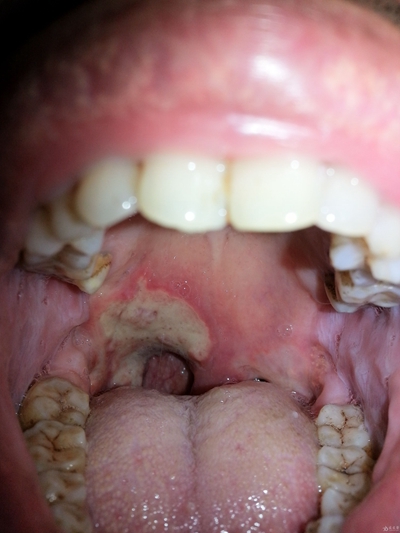

口腔癌圖片

口腔癌的前兆 (46)

口腔癌的前兆 (47)

口腔癌的前兆 (48)

口腔癌的前兆 (49)